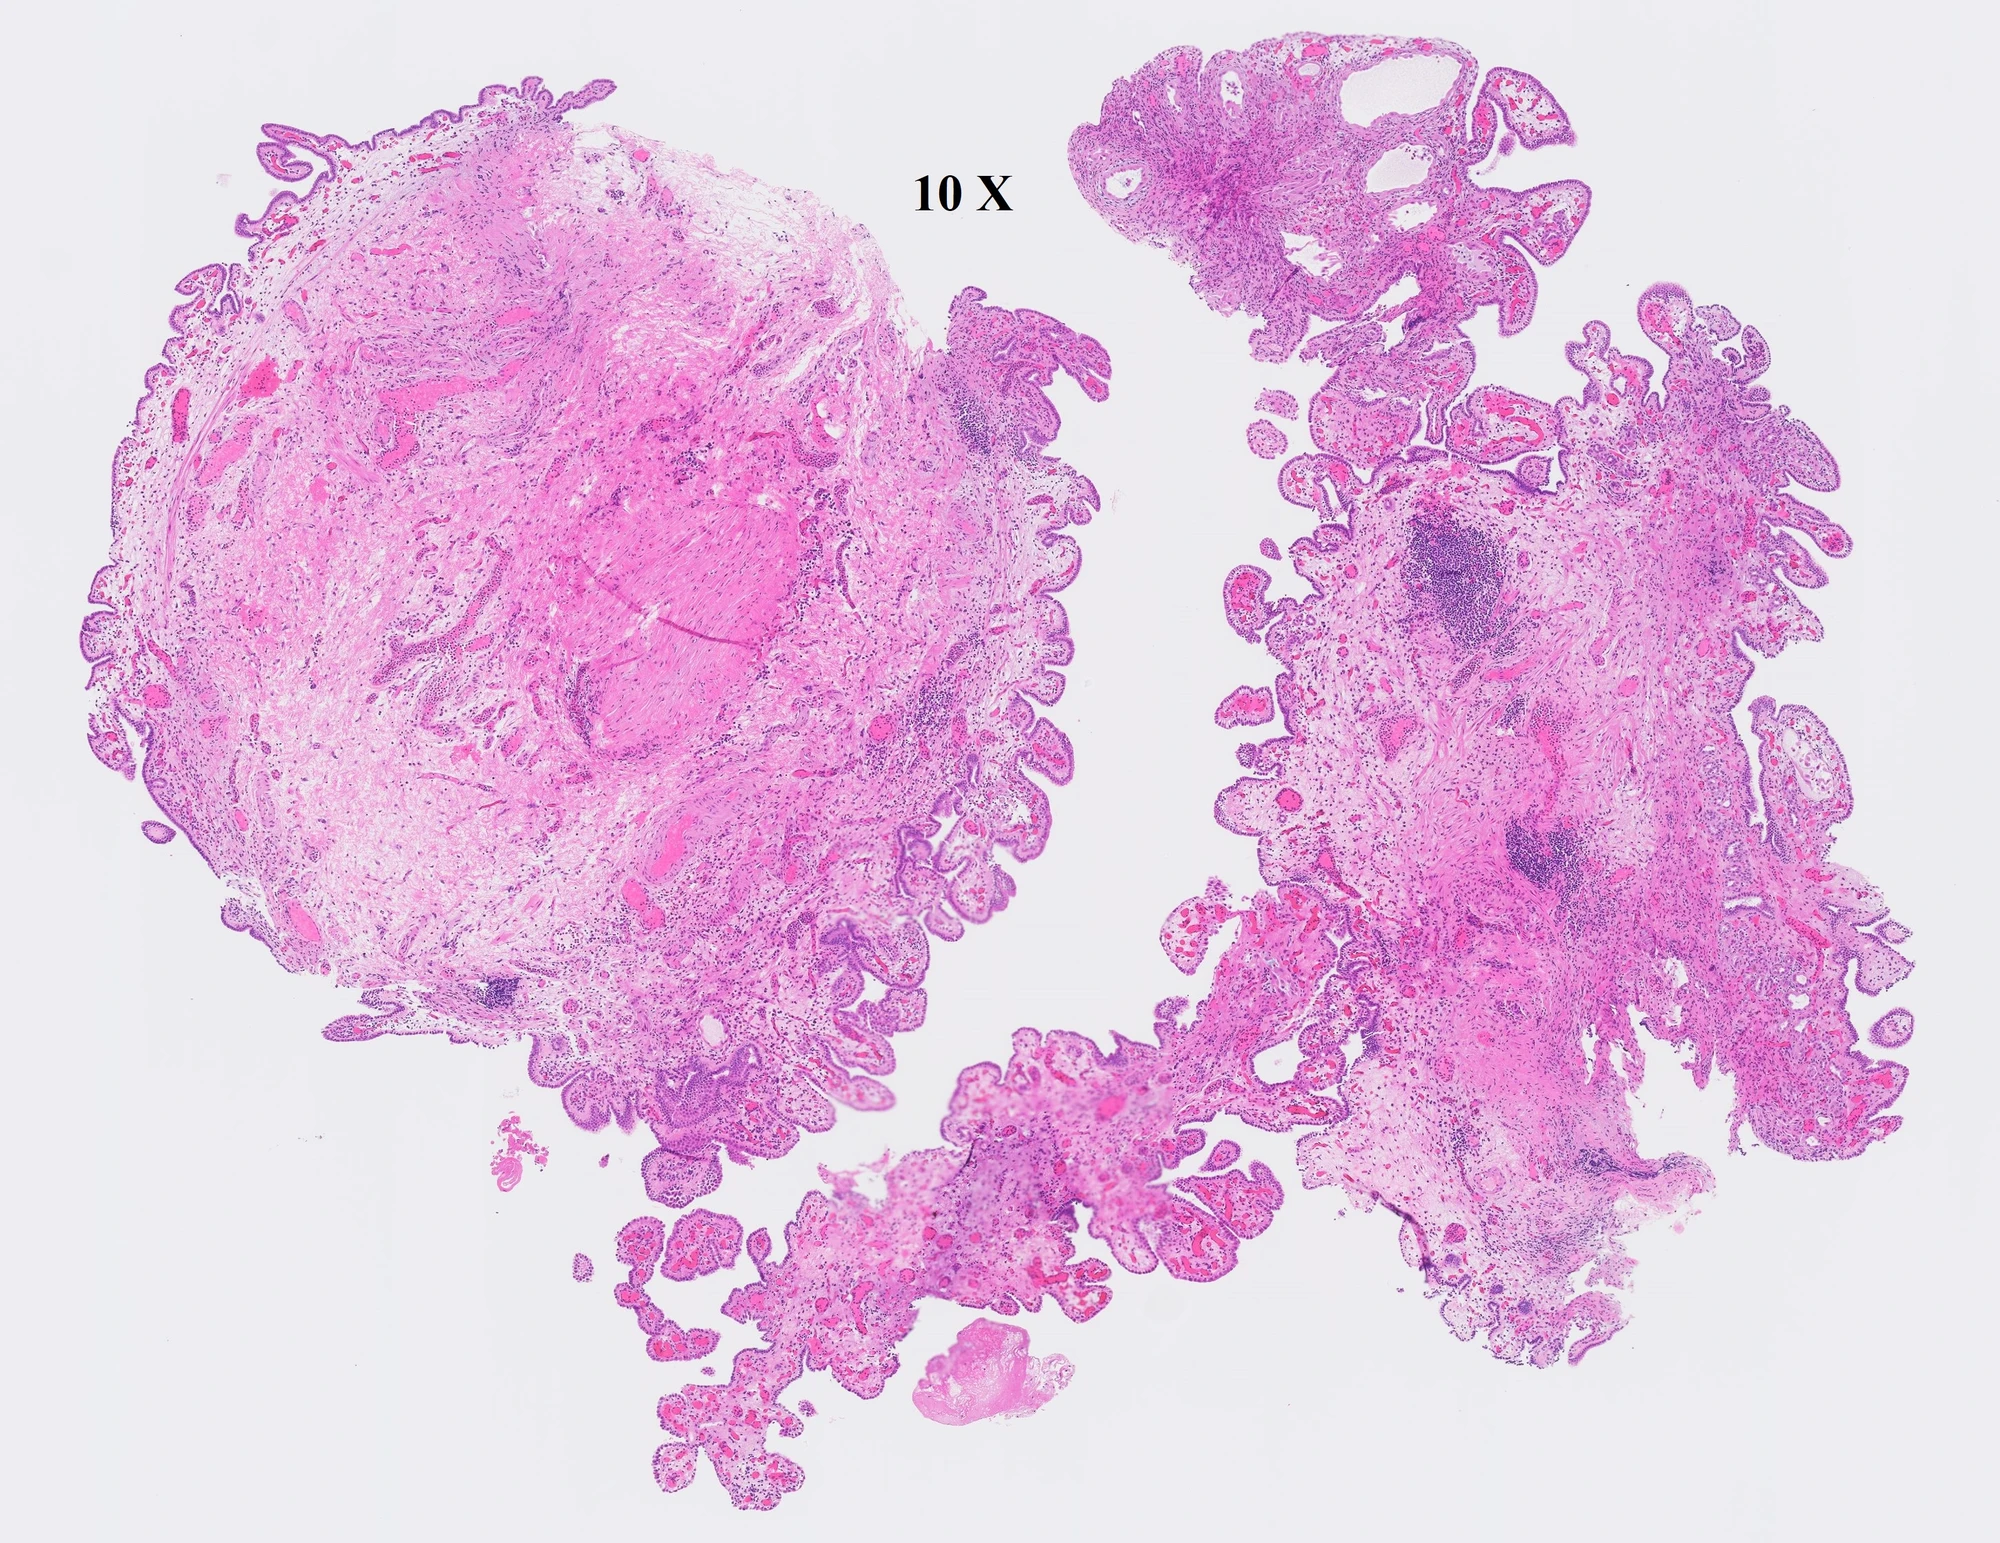

What is the most likely diagnosis?

- Nephrogenic Adenoma of Bladder

- Urothelial Papilloma

- Papillary urothelial neoplasm with low malignant potential

- Low-grade papillary urothelial carcinomas

Nephrogenic Adenoma of Bladder